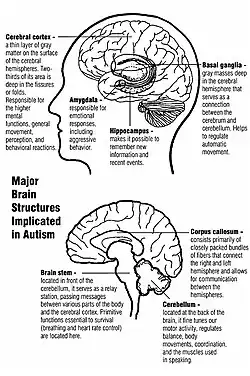

Structure cérébrale

Des différences au niveau du cerveau ont été observées chez les personnes autistes, apportant une signature anatomique à la définition antérieure par des critères cliniques. Les études en neurosciences ont montré des différences dans l’organisation du cortex[38],[39], au niveau des dendrites (arborescences des neurones) et des synapses (connexion entre neurones), voire des modifications plus larges de structures cérébrales. Il est possible que les différences corticales apparaissent au cours d'un stade de développement anténatal[38].

En corrélation avec les différences fonctionnelles observées au niveau comportemental, les études d'Eric Courchesne et de son équipe relèvent que les enfants autistes ont un nombre de neurones plus élevé de 67 % en moyenne dans le cortex préfrontal[40], et une croissance cérébrale plus importante que la moyenne au niveau des lobes frontaux, ce qui s'est traduit dans la littérature scientifique antérieure par des observations de périmètre crânien plus élevé[41].

Cependant, le , dans une étude basée sur des données par imagerie par résonance magnétique (IRM), des chercheurs de l'Université Ben-Gourion du Néguev et de l'Université Carnegie-Mellon (États-Unis) ont estimé que les différences anatomiques entre le cerveau de personnes autistes de plus de 6 ans et celui de personnes du même âge non autistes sont indiscernables[42],[43]. Pour arriver à ce résultat, ces chercheurs ont utilisé la base de données Autism Brain Imaging Data Exchange (ABIDE), qui a permis pour la première fois de procéder à des comparaisons de grande échelle de scanners IRM entre des groupes de personnes autistes et des groupes contrôle[44]. Cette base de données est une collection mondiale de scanners IRM de plus de 1 000 personnes, pour la moitié autistes, âgés de 6 à 35 ans[45].

L'Institut de neurosciences de la Timone (Marseille, France) a identifié un marqueur anatomique spécifique de l'autisme, détectable par IRM et présent dès l'âge de deux ans. Ce marqueur consiste en un plissement spécifique du cortex cérébral. Il est appelé « racine du sillon »[46],[47],[48].

À l'échelle des synapses, des études mettent en évidence des modifications dans le système des neurotransmetteurs, en particulier celui du transport de la sérotonine en association notamment avec des modifications de gènes impliqués. L'implication du système dopaminergique ou glutamatergique semble moins bien démontrée. Enfin, des études sont en cours en 2009 sur le rôle du système cholinergique, de l'ocytocine ou de certains acides aminés impliqués dans la neurotransmission[49].